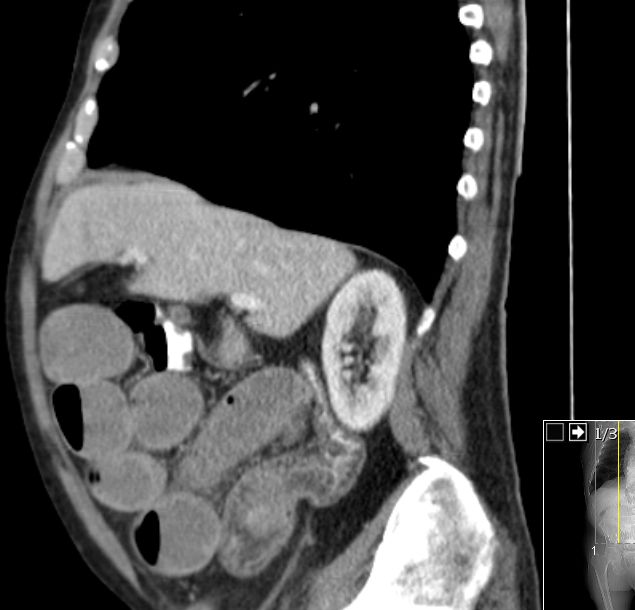

Colon 74-jähriger Mann mit Ileus durch einen Tumor im Colon ascendens.

Histologie: gut differenzierter neuroendokriner Tumor, G1, Ki67 unter 1%.